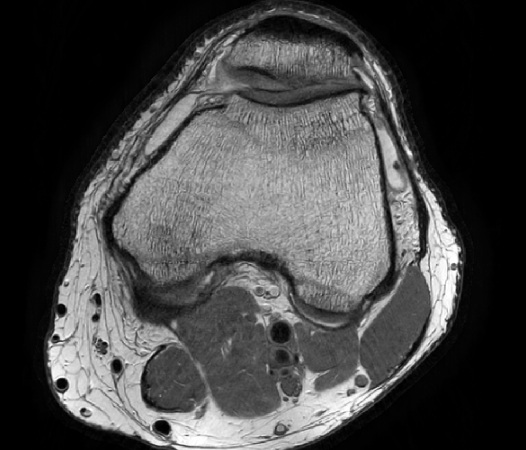

The Compressed SENSE reconstruction then uses iterative, knowledge-based algorithms to fill in the empty lines in k-space (bottom left). This removes the artifacts while keeping the final image fully consistent with the acquired data (bottom right).

Knee compressed sense